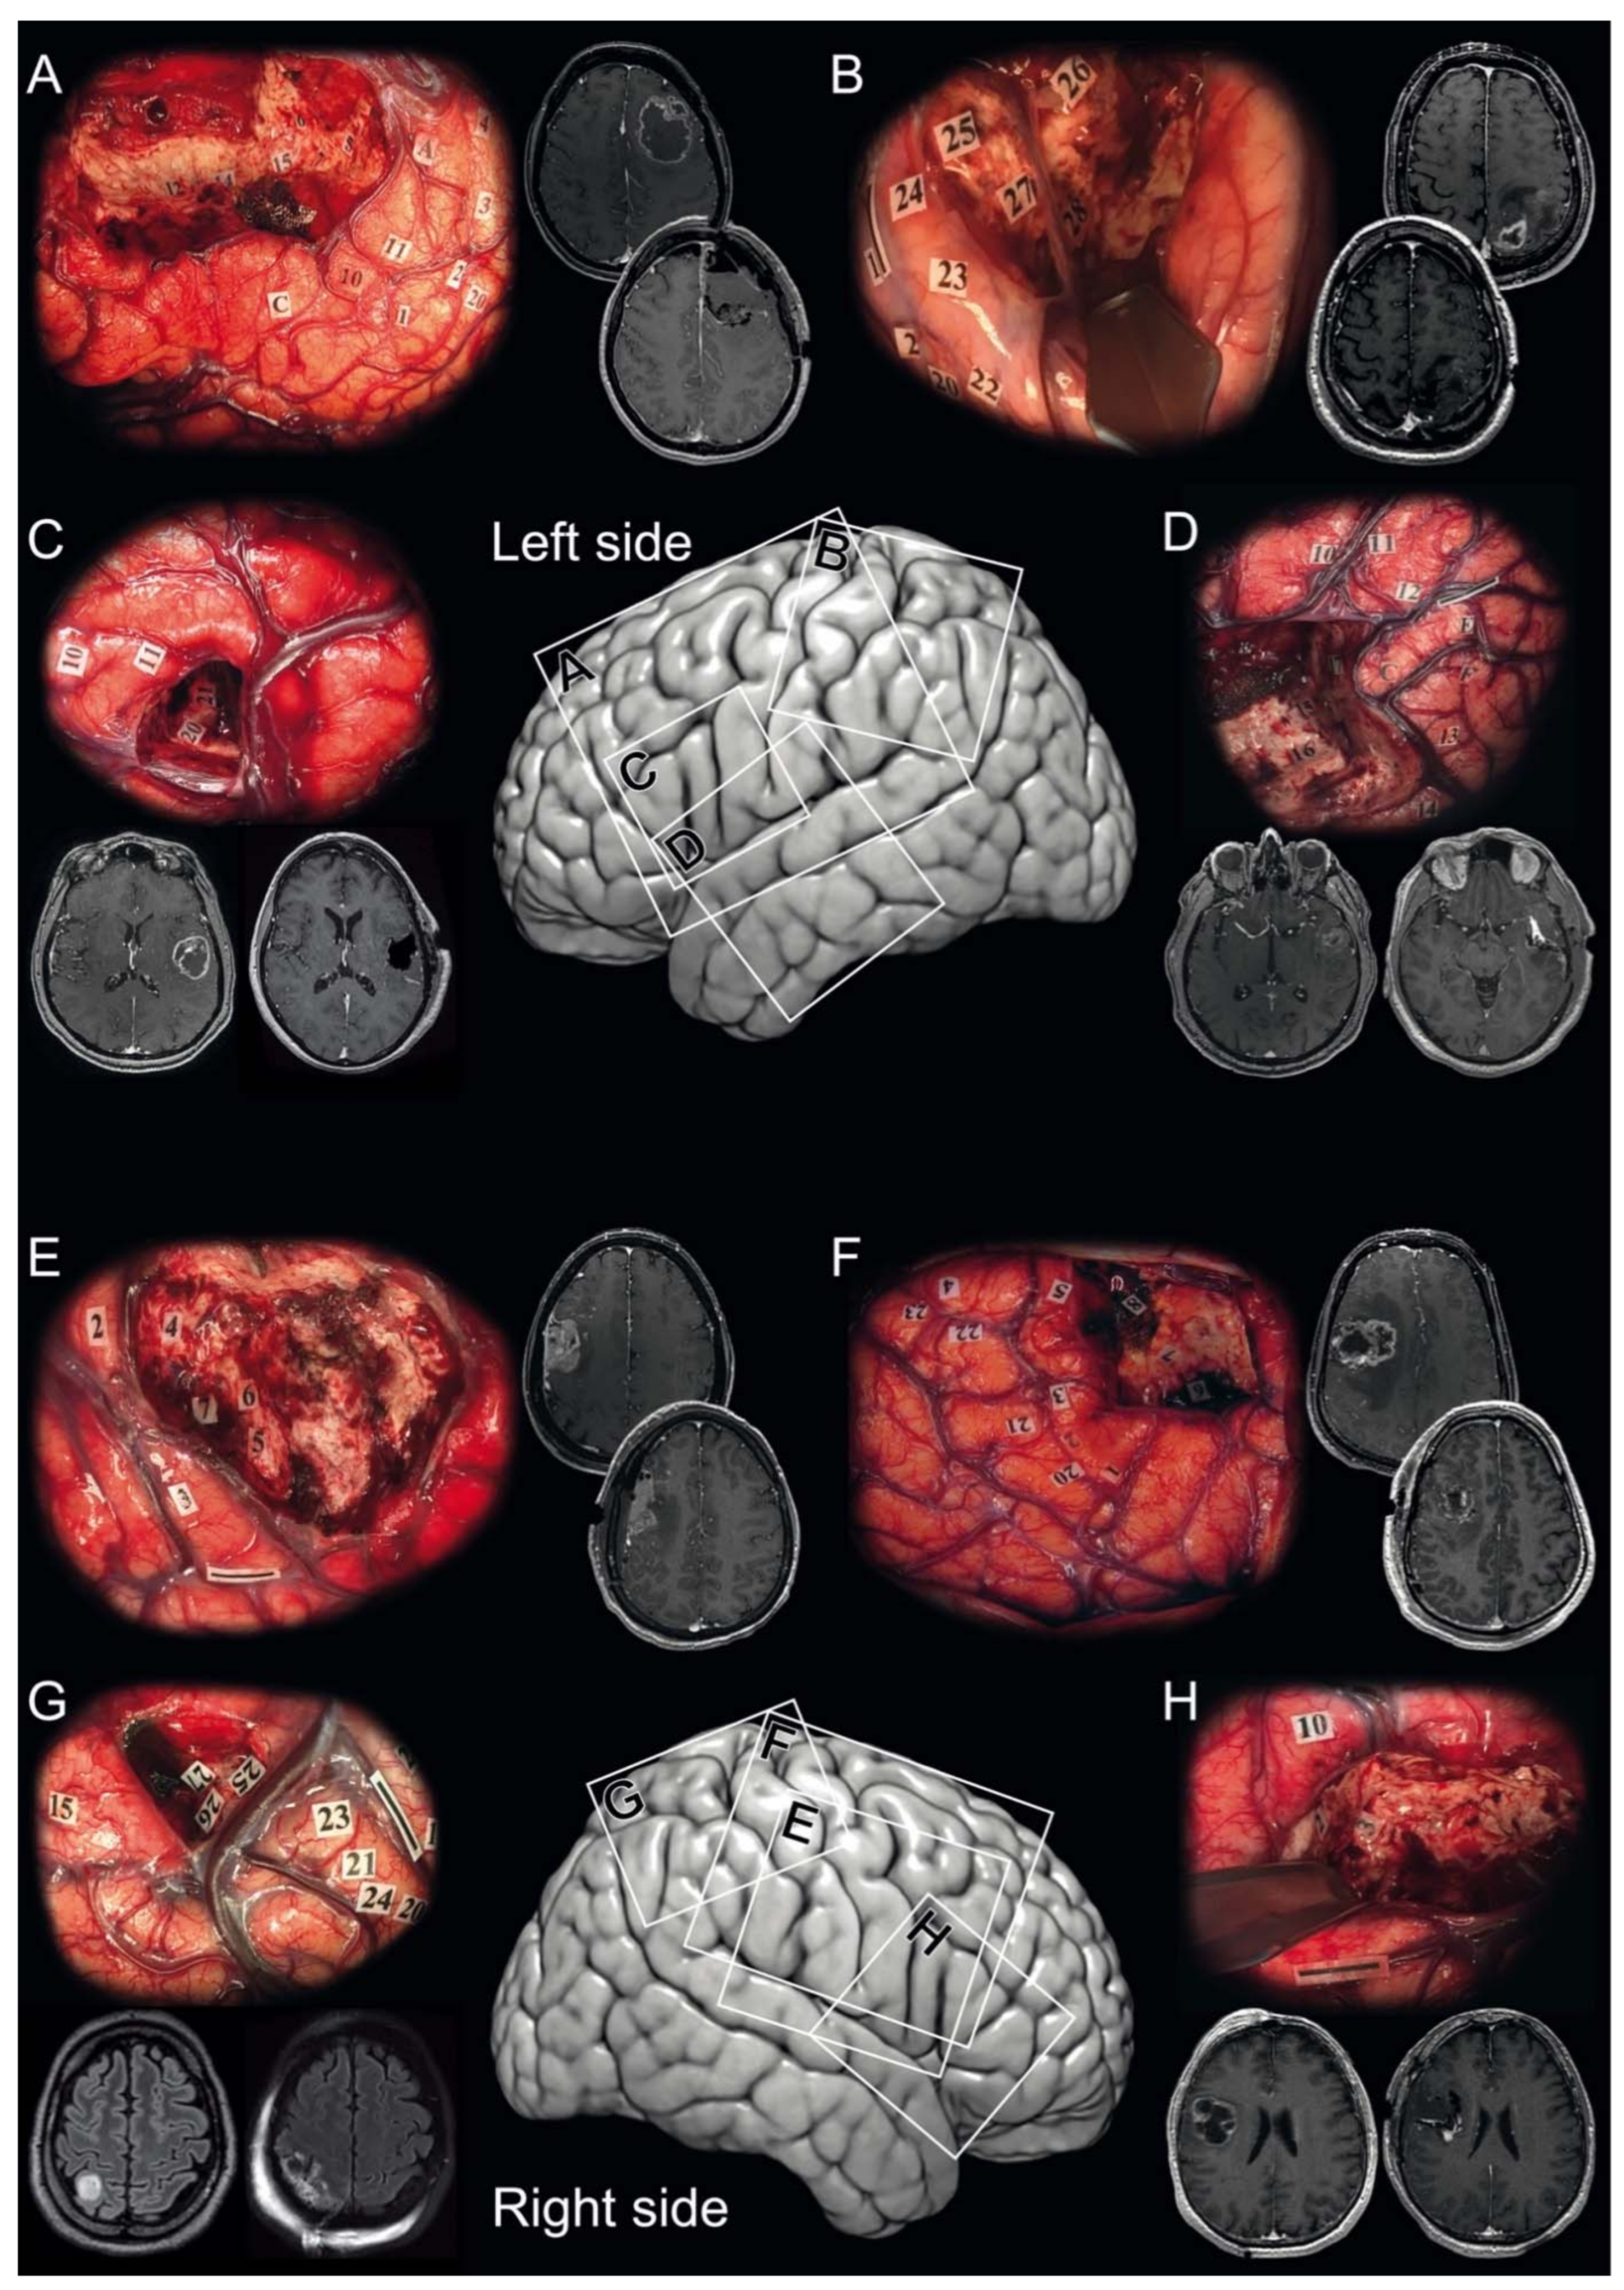

3.2. Awake Surgery Procedure

- Pallud, J.; Rigaux-Viode, O.; Corns, R.; Muto, J.; Lopez, C.L.; Mellerio, C.; Sauvageon, X.; Dezamis, E. Direct electrical bipolar electrostimulation for functional cortical and subcortical cerebral mapping in awake craniotomy. Practical considerations. Neurochirurgie 2017, 63, 164–174. [Google Scholar] [CrossRef] [PubMed]

- Pallud, J.; Mandonnet, E.; Corns, R.; Dezamis, E.; Parraga, E.; Zanello, M.; Spena, G. Technical principles of direct bipolar electrostimulation for cortical and subcortical mapping in awake craniotomy. Neurochirurgie 2017, 63, 158–163. [Google Scholar] [CrossRef] [PubMed]